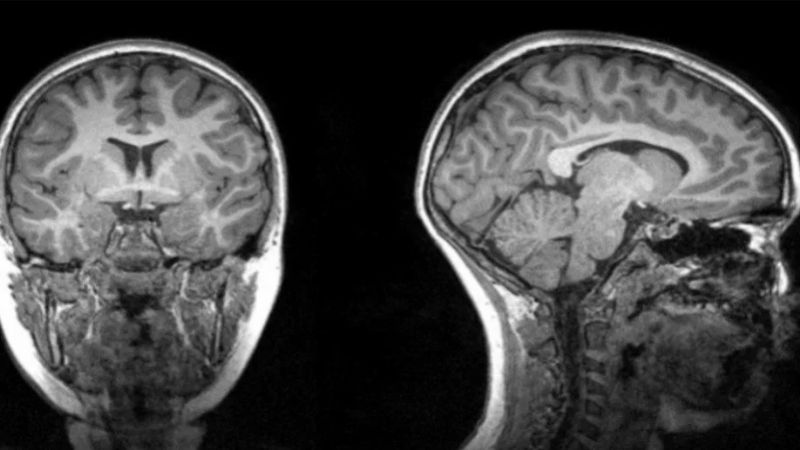

Ahora, un nuevo estudio a cargo de la Universidad Estatal de Georgia y el Instituto de Ternología de Georgia, en Estados Unidos, descubrió que los pacientes que se sometieron a terapia con oxígeno y que tuvieron altas temperaturas muestran un volumen reducido de materia gris en la región frontal-temporal del cerebro.

Esta investigación reveló que esta disminución del volumen de materia gris estaba asociada con el Covid-19. Y que se puede desarrollar hasta seis meses después de haber recibido el alta.

Los especialistas se valieron de tomografías computarizadas de 120 pacientes neurológicos, 58 de ellos positivos de Covid y 62 que formaban el grupo control.

Además, los investigadores encontraron que el volumen de materia gris en esta región se redujo significativamente más en los pacientes que recibieron oxigenoterapia en comparación con los pacientes que no la recibieron. Lo mismo ocurrió con los pacientes que presentaron fiebres altas.

Es por ello que llegaron a la conclusión que el Covid puede afectar la región frontal-temporal a través de fiebre o falta de oxígeno.